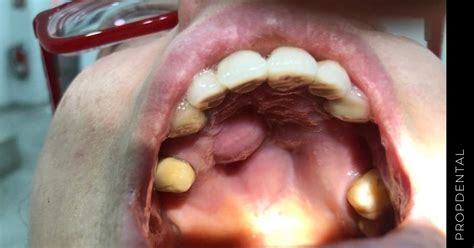

Causas Comunes de Bultos en el Paladar

Existen diferentes tipos de bultos en el paladar. Algunos ocasionan dolor o molestias. Aquí te presentamos algunas de las causas más comunes:

- Quistes Mucosos: Son bultos no cancerosos que pueden aparecer en cualquier parte de la boca, incluyendo el paladar. Un quiste mucoso es un saco indoloro y delgado que contiene un líquido transparente y se sitúa en el paladar.

- Torus Palatino: El torus palatino es un crecimiento óseo benigno que aparece en el centro del paladar. Muchas personas lo tienen y ni siquiera lo saben. El torus palatino es una protuberancia ósea de apariencia dura. Suele tener una causa genética, es asintomático y no duele. Un torus es duro, está ubicado generalmente en el centro del paladar, no duele al tocarlo y lleva tiempo ahí.

- Mucocele: Un mucocele es un pequeño bulto blando causado por la obstrucción de glándulas salivales menores. Suele tener un aspecto azulado o translúcido y generalmente es indoloro. El mucocele se genera por la acumulación de moco o por una alteración de las glándulas salivales del paladar. Se trata de un bulto blando, inflamado y con crecimiento muy lento. En algunas ocasiones, llega a desaparecer por sí solo.

- Absceso Palatino: Un absceso palatino es una acumulación de pus que se forma en la zona del paladar debido a una infección bacteriana. Un absceso en el paladar es una infección localizada con acumulación de pus que se forma debido a la presencia de bacterias. Si el bulto en tu paladar va acompañado de dolor, mal sabor o sensación de “pulsación”, es muy probable que sea un absceso. Un absceso es un pequeño bulto o inflamación que se localiza cerca de algún diente.

- Papilomas: Similar a una pequeña verruga en la boca, los papilomas son crecimientos benignos que pueden aparecer en cualquier parte de la cavidad oral, incluido el paladar.

- Granuloma Piogénico: El granuloma piogénico suele aparecer en mujeres embarazadas y tiende a localizarse en la mitad del paladar. Se trata de un abultamiento rosado, blando y de consistencia fina. Además, si se irrita puede llegar a sangrar. El granuloma piogénico es una pequeña protuberancia que aparece en el centro del paladar, con un color rojizo o rosado de consistencia fina, lo que hace que pueda llegar a sangrar debido a que se produce una irritación.

- Adenoma Pleomorfo: El adenoma pleomorfo es un tumor benigno de las glándulas salivales. Se manifiesta mediante un bulto o masa que se localiza, normalmente, a los lados de la línea media del paladar. Tiene un crecimiento muy lento y, además, no resulta doloroso. El adenoma pleomorfo es un tumor benigno que aparece en los extremos de la línea media del paladar.

- Tumores Malignos: El tumor maligno se presenta como un abultamiento similar al anterior. Sin embargo, tiene un crecimiento mucho más rápido y doloroso. De todos los tipos mencionados, este último es, sin duda, el más complejo de tratar. Un bulto en el paladar puede que no signifique nada grave, como ser solo la señal de alguna infección, aunque hemos visto que en otros casos puede llegar a indicar incluso un cáncer de boca.

- Leucoplasia: La leucoplasia es una anomalía que aparece en la boca en forma de una especie de parches blancos y gruesos. Estos se ubican en las superficies internas de la boca, entre ellas el paladar. Las causas pueden ser muy variadas, pero entre las principales se encuentran la repetición de lesiones o irritación y, en el peor de los casos, es la señal de cambios precancerosos o cáncer en la boca.

- Quiste Odontogénico Glandular (QOG): El quiste odontogénico glandular (QOG) es una lesión quística poco frecuente que se caracteriza por bultos de pequeño tamaño y en zonas cercanas a los dientes.

- Estomatitis: La estomatitis es una infección viral de la boca que ocasiona llagas y úlceras que pueden ubicarse en el paladar.